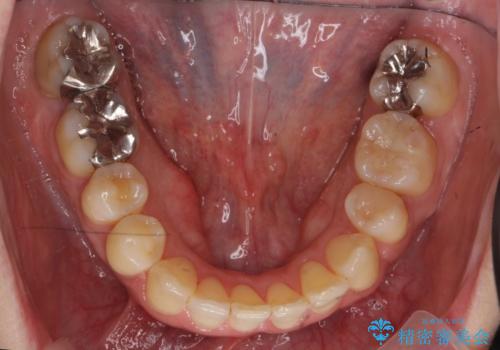

40代の矯正 八重歯を綺麗に

矯正用のミニスクリューを使用し、また、前歯をIPRすることで正中の左へのずれを最小限に抑えています。

上の前歯が内側に入っているクロスバイトは、笑った時に影になってしまい、かなり目立ちます。

内側に入っている前歯を外に出すだけで劇的に印象が変わります。